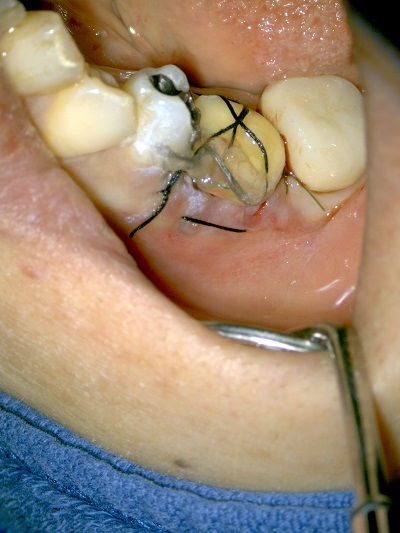

外科的根管治療とはそういった場合にマイクロスコープを用いて歯根の外側から根管の掃除を行い、封鎖する方法です。歯肉を開き、骨を僅かに削って、歯根先端を3mm程切断し、歯根側から根管の中をきれいにし、MTAセメントを詰めて封鎖を行います。

自家歯牙移植は移植歯(ドナーの歯)の状態と移植部位の骨の状態などがマッチした場合有効な方法です。しかしながら移植歯の歯根膜組織の扱いや移植後の固定、根管治療などを適正におこなわなければならず、しっかりとした治療計画と術中、術後管理が必要となります。

Step-4 移植歯の固定

(移植歯がしっかりと生着するまで1から2ヶ月固定をおこないます)